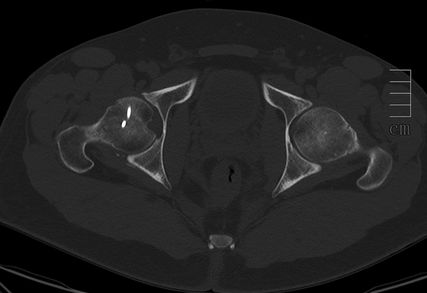

Abb. 3: Zur präoperativen Planung und zur Beurteilung des geschlossenen Repositionsergebnisses ist der Goldstandard die Computertomografie

Neben der klinischen Erstuntersuchung und Anamnese umfasst die Diagnostik die konventionelle native Röntgendiagnostik des verletzten Hüftgelenkes mit Standardaufnahmen im a.-p. und axialen Strahlengang (Abb. 1, 2) sowie gegebenenfalls die Anfertigung von Ala- und Obturatoraufnahmen. Obligatorisch empfehlen wir die Anfertigung eines Hüftübersichtsröntgens und gegebenenfalls, sofern möglich, auch eine Faux-Profil-Aufnahme. Zur präoperativen Planung und zur Beurteilung des Repositionsergebnisses ist der Goldstandard die Computertomografie (Abb. 3) mit Anfertigung einer 3D-Rekonstruktion. Im Rahmen der Notfalldiagnostik spielt die Magnetresonanz keine wesentliche Rolle. Im Hinblick auf die Diagnostik sekundär auftretender Komplikationen ist jedoch die Bedeutung des MRT unumstritten.